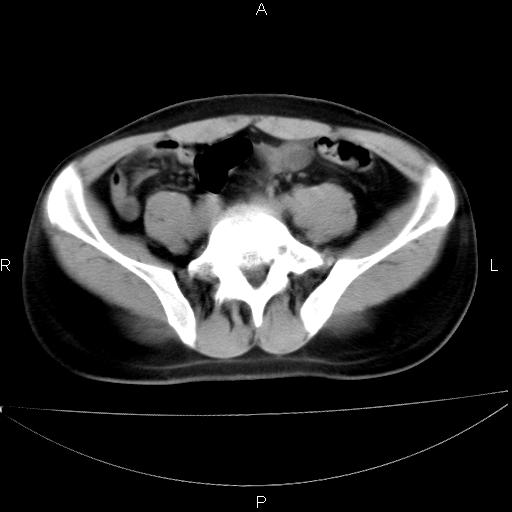

男 25岁 自述 尿频尿急,排尿困难20多天.无腰痛, b超说左肾盂轻度积水,左输尿管上端扩张.未见结石影. ct我看双侧肾盂轻度积水,双输尿管上端都扩张,大家看看能看见结石吗?

双肾轻度积水,未见明确结石,薄层对结石检出率较高。

要排除upj,可做ivp造影

双侧输尿管上端扩张,未见明确结石,可进一步ivp检查。

考虑肾外肾盂 前列腺轻度肿大 密度欠均 考虑炎性改变